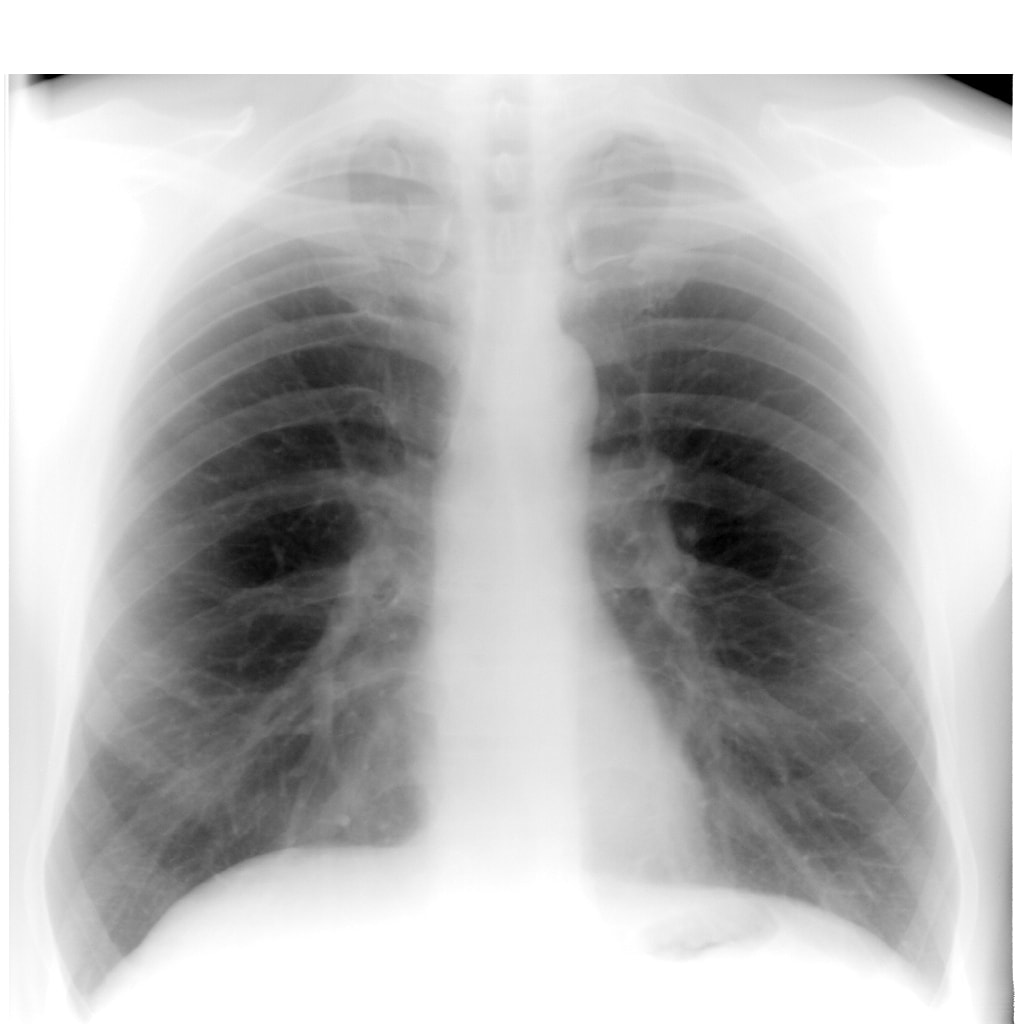

Рентгеновский снимок лёгких

Рентген лёгких и бронхов показывает осложнения, возникшие на его фоне. При наличии у пациента непосредственно воспалительного процесса в бронхах, на снимке будут заметны следующие особенности:

- усиление лёгочного рисунка — лёгочный рисунок представляет собой тень от кровеносных сосудов. Усиление лёгочного рисунка провоцирует патологические изменённые бронхи, которые в норме практически не видны;

- утолщение стенок бронхов — наиболее специфический признак, который видно на снимке лёгких. Он является определяющим в совокупности с другими данными исследования при постановке диагноза. Хронический бронхит

Бронхит на рентгеновском снимке